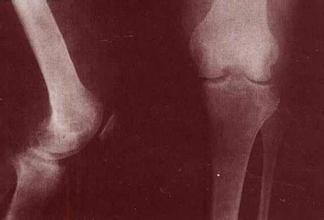

导读: 膝关节是全身关节中滑膜面积较大的关节,滑膜反应也较明显。膝关节创伤性滑膜炎是指膝关节囊纤维的内衬滑膜在外伤后引起的滑膜非感染性炎症反应。临床上分为急性创伤性炎症和慢性劳损性炎症两种。若确诊为本病应积极